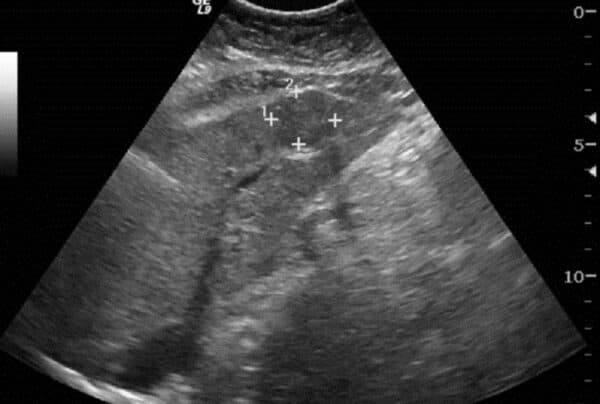

– Làm những xét nghiệm kiểm tra tình trạng ung thư gan: Điều này nhằm xác định tình trạng của bệnh để kịp thời đưa ra hướng xử lí, những xét nghiệm có thể bao gồm: nồng độ AFP trong máu, xét nghiệm đánh giá chức năng của gan như: AST, ALT, GGT, xét nghiệm tầm soát viêm gan B, C chi tiết… Hoặc có thể chẩn đoán hình ảnh thông qua: siêu âm, chụp CT, sinh thiết…

Siêu âm là một phương pháp để đánh giá tình trạng bệnh ung thư gan